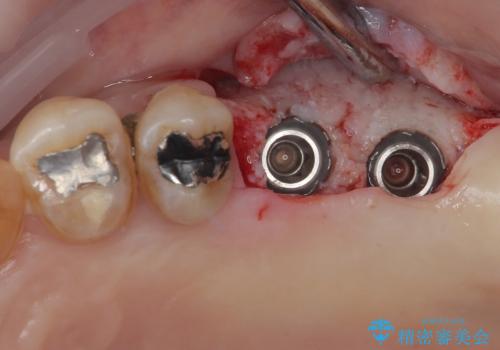

数年前まで当院でも行われていた従来の手法では、骨補填材による上顎洞底の挙上を行い、インプラント埋入に半年以上の期間を必要とするものでした。

しかしながら、ここ数年で流通してきたデンサーバーというドリルと、エキストラワイドショートインプラントの併用により、骨補填材による上顎洞底の挙上なしに埋入が行えるようになりました。

元々の骨量が少なく、通常よりは待機期間が長くなりますが、数ヶ月程度で補綴治療まで行うことができるため、こちらの手法でインプラント補綴治療を行うこととしました。